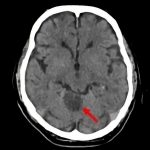

Brain tumor

病名

断層撮影

手術前1

手術前2